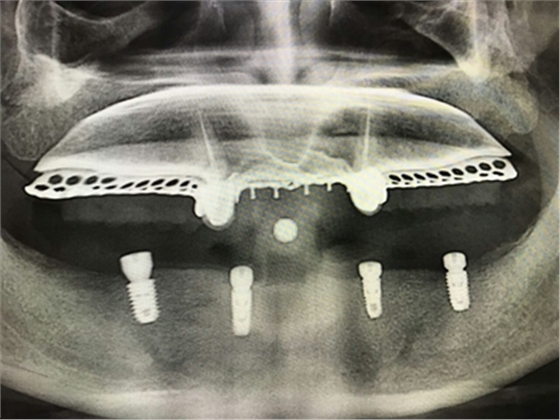

毛國(guó)斌種植病例——群討論分享

Screenshot_2017-04-25-09-45-02.pngScreenshot_2017-04-25-09-46-19.pngScreenshot_2017-04-25-09-51-57.pngScreenshot_2017-04-25-09-52-41.pngScreenshot_2017-04-25-10-06-38.pngScreenshot_2017-04-25-10-09-20.png

Screenshot_2017-04-25-10-12-47.pngScreenshot_2017-04-25-10-16-29.pngScreenshot_2017-04-25-10-19-08.pngScreenshot_2017-04-25-10-22-02.pngScreenshot_2017-04-25-10-26-11.pngScreenshot_2017-04-25-10-26-35.png

Screenshot_2017-04-25-10-34-15.pngScreenshot_2017-04-25-10-37-02.pngScreenshot_2017-04-25-10-38-17.pngScreenshot_2017-04-25-10-43-56.pngScreenshot_2017-04-25-10-45-02.png

mmexport1493090938783.jpgmmexport1493090943165.jpg

mmexport1493090947523.jpgmmexport1493090952079.jpg

mmexport1493090960504.jpgmmexport1493090963186.jpg

mmexport1493090967371.jpgmmexport1493090969886.jpg

mmexport1493090972304.jpgmmexport1493090974802.jpg

mmexport1493090981101.jpg

mmexport1493090983321.jpgmmexport1493090991830.jpg

mmexport1493090994026.jpgmmexport1493090985721.jpg

mmexport1493091008273.jpgmmexport1493091010574.jpg

江思玉整理群種植病例